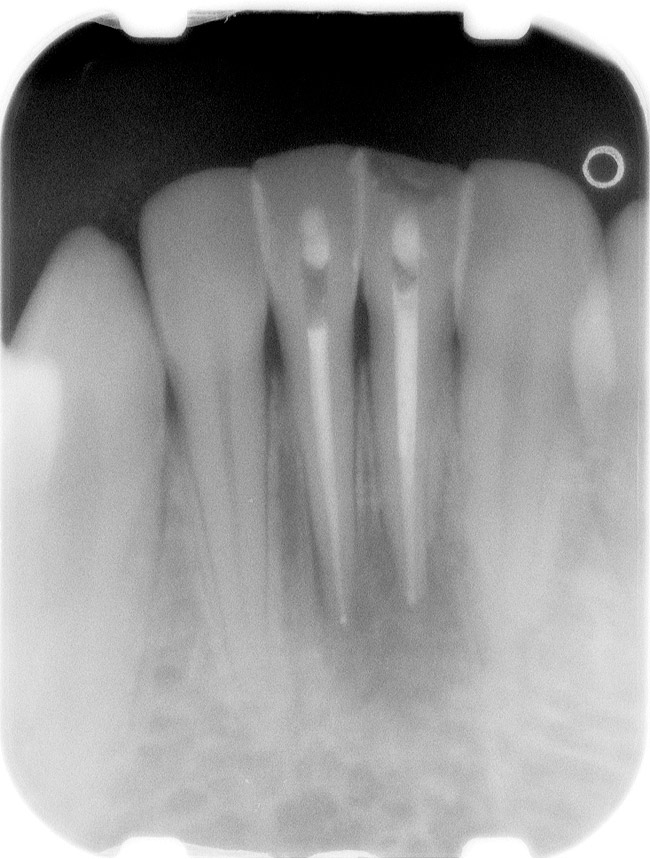

Figure 1  X-ray of an endodontically treated second bicuspid restored with a fiber post, core, and all-porcelain crown.

Figure 1

Figure 2  Same second bicuspid as Figure 1 after removal of the fractured fiber post.

Figure 2

Case 1

A Class IN maxillary bicuspid was previously restored with a fiber post and an all-porcelain crown (Figure 1). The forces of the oral environment resulted in fracture of the fiber post and crown failure. The remaining fiber post in the root was removed, and anti-rotational areas were prepared for a cast post (Figure 2). A gold cast post was constructed at a dental laboratory, using an indirect technique (Figure 3). A porcelain-fused-to-metal (PFM) crown was constructed with a bevel finish to provide a ferrule and reduce forces on the post (Figure 4 and Figure 5).